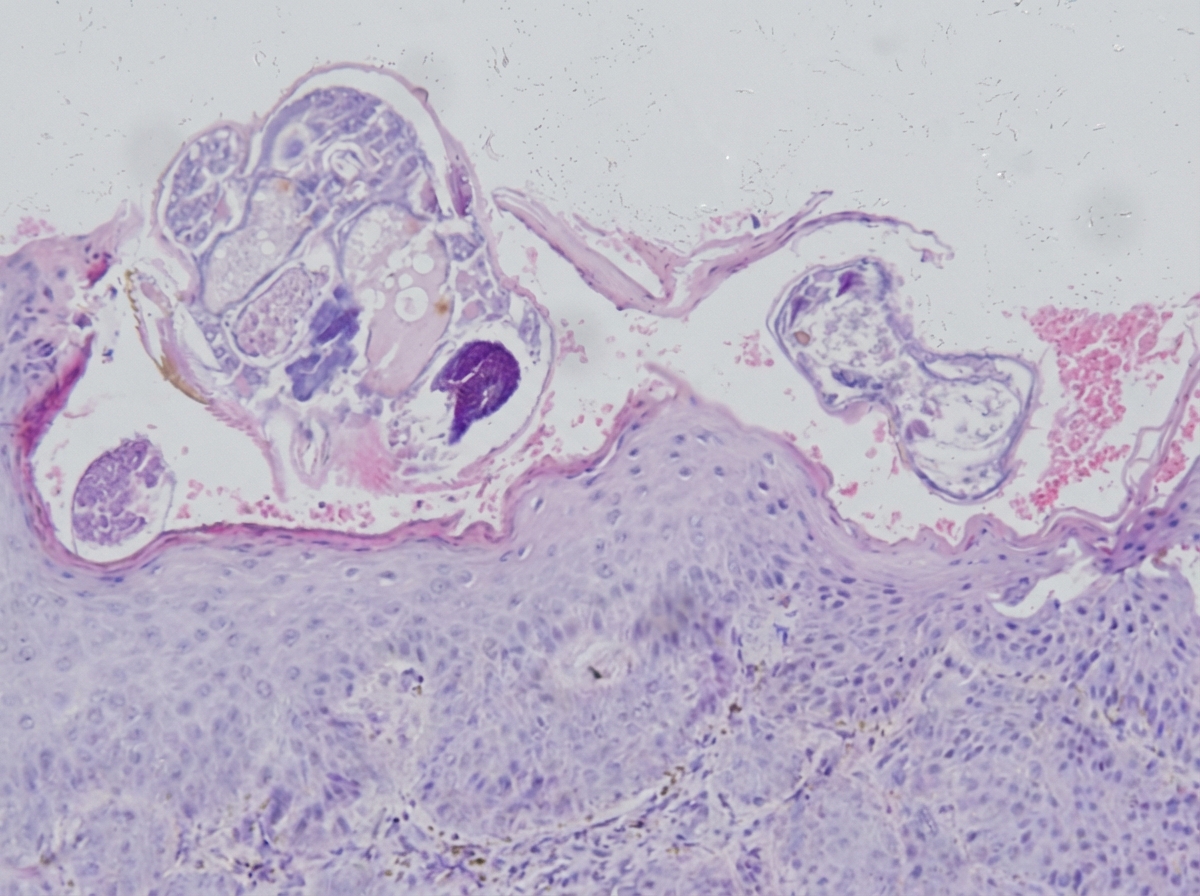

A 37-year-old woman with a history of systemic lupus erythematosus, on prednisone and methotrexate, presents to the dermatology clinic with three weeks of a diffuse, itchy rash. Physical exam is remarkable for small red papules in her bilateral axillae and groin and thin reddish-brown lines in her interdigital spaces. The following skin biopsy is obtained. Which of the following is the most appropriate treatment?